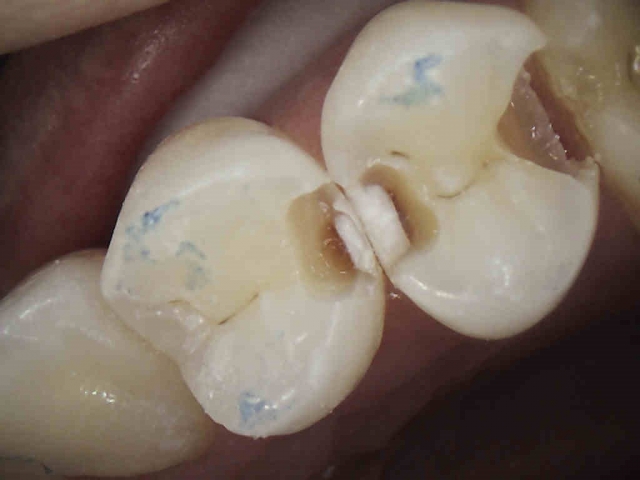

Patient 5: Tooth #18

This patient was referred from a periodontist who was going to extract #19 with socket preservation. The black and white image is deceiving, as they can be sometimes. Here, the mesial does not show a definitive lesion. It is here that the clinical examination is key. Do you examine and chase cracks? If a marginal ridge has a crack that is palpable to your explorer and is discolored, it is leaking. The photo image shows this well. The image that follows shows quite a different story than the black-and-white image. Notice the crack mid-prep is still quite prevalent.